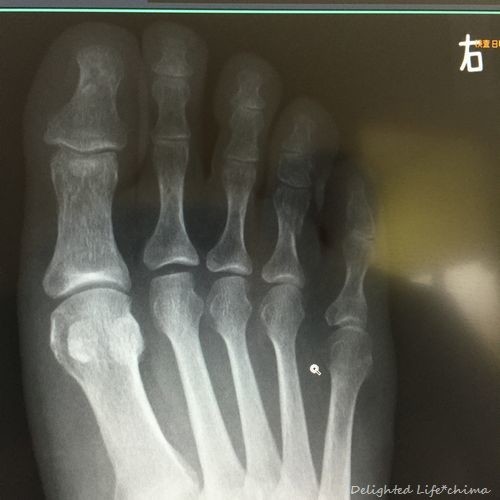

足の指 骨折 Delighted Life クックパッドブログ

足指骨折 2日目 35歳 美容と食べ物中心ブログ

足指骨折 11日目 35歳 美容と食べ物中心ブログ